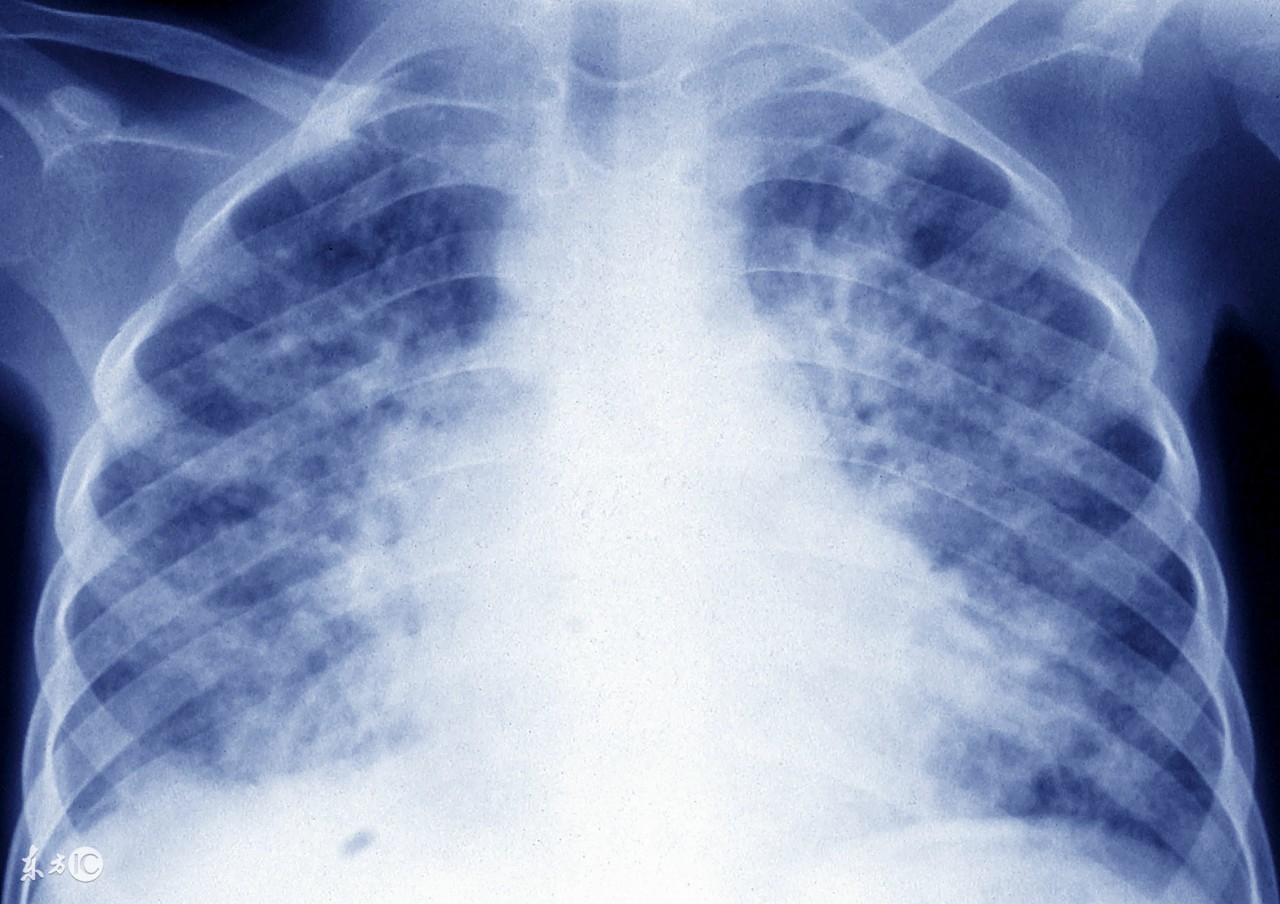

若胸片有异常,应到肺科专科医院进一步详细检查,切忌草率下结论“陈旧性肺结核”,是否“陈旧”需经过一系列检查才能确定的,比如PPD皮试、痰结核菌、胸部CT等,所谓“陈旧性肺结核”其中一些是活动性的,是肺结核早期、或陈旧肺结核复发了。